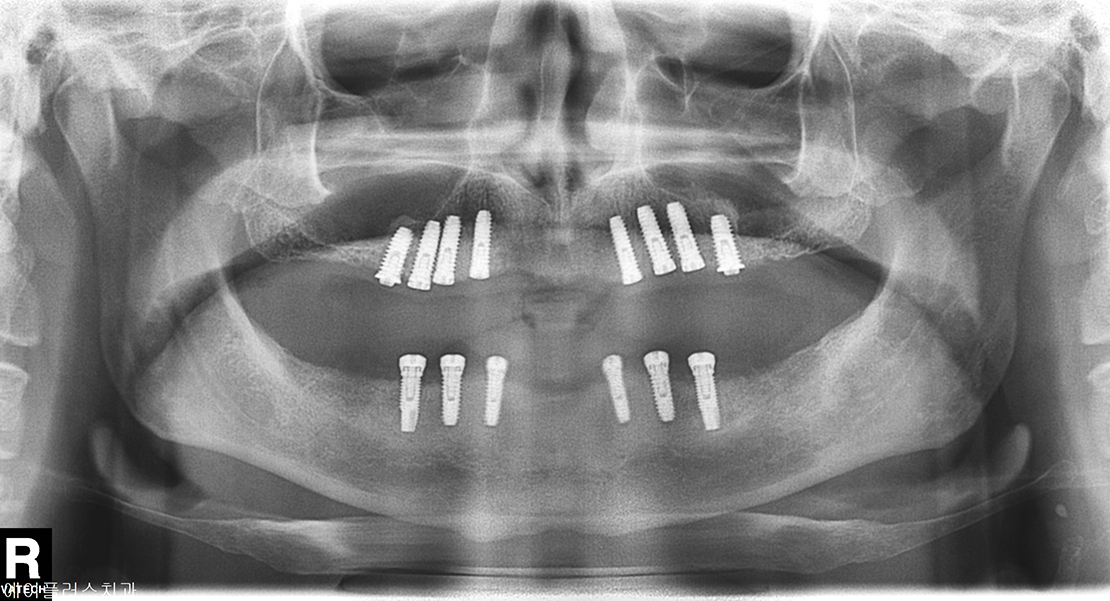

Before Treatment

Implant Placed